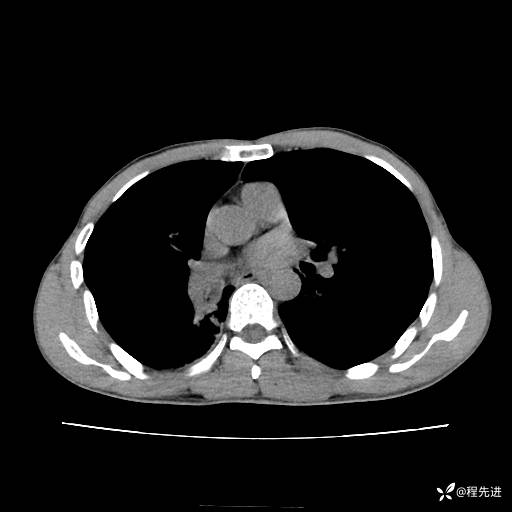

患者性别:男

患者年龄:49岁

主诉:咳嗽、胸痛1周

简要病史:1周前受凉感冒后开始出现咳嗽症状,阵发性连声咳,痰多,黄白痰,不易咳出,伴胸痛、气紧、胸闷,右侧为主,活动用力、呼吸时胸痛明显,曾在当地诊所贴敷膏药仍疼痛

体格检查:T:36.3 ℃ P:80 次/分 R:20 次/分 BP:120/88 mmHg,指脉氧饱和度97%,意识清晰,呼吸平稳,右侧第二、三肋骨压痛,可见膏药贴敷,皮肤无异常,双肺呼吸音粗,未闻及干湿性啰音。心率80次/分,节律整齐,无杂音。腹平软,全腹无压痛无反跳痛

临床诊断:社区获得性肺炎

CT平扫: